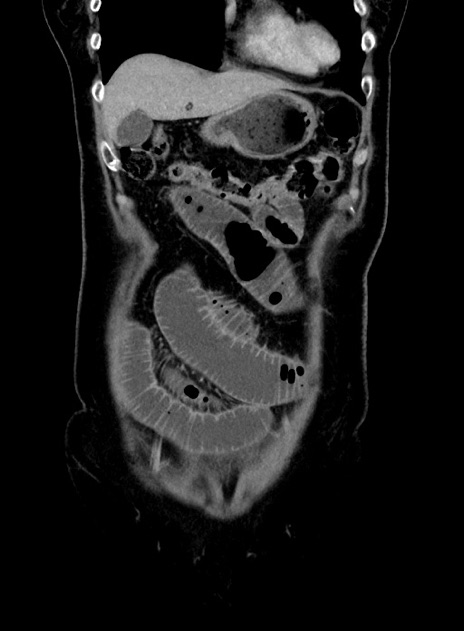

症例9(冠状断像)

【症例】 60歳代女性

【主訴】むかつき、みぞおちの痛み

【現病歴】3日前よりむかつきがあり、食事がとれない。

【既往歴】糖尿病

【身体所見】発熱なし、心窩部圧痛軽度あるも、腹膜刺激症状なし。

【データ】WBC 7400、CRP 1.92